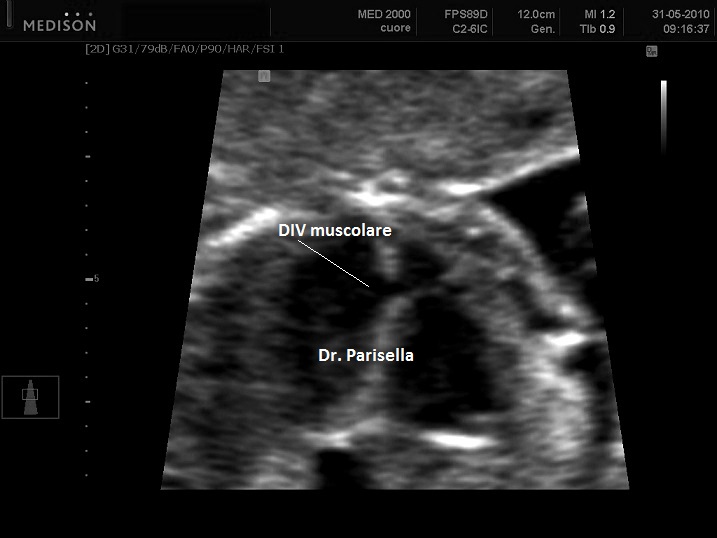

Possono essere presenti: idrope, cardioaptie congenite, labiopalatoschisi, oligoamnios, anomalie genito-urinarie, anomalie gastro-intestinali, anomalie del SNC.

Sono frequenti le cardiopatie congenite. Possono essere presenti anomalie genitourinarie e gastrointestinali. I femori hanno le estremità appuntite.

Sono frequenti le cardiopatie congenite e la labiopalatoschisi mediana. La polidattilia è preassiale e interessa mani e piedi. Può essere presente oloprosencefalia e genitali ambigui.

Sono presenti labiopalatoschisi, anomalie genitourinarie ed anomalie gastrointestinali. Può essere presente idrope ed ascite.